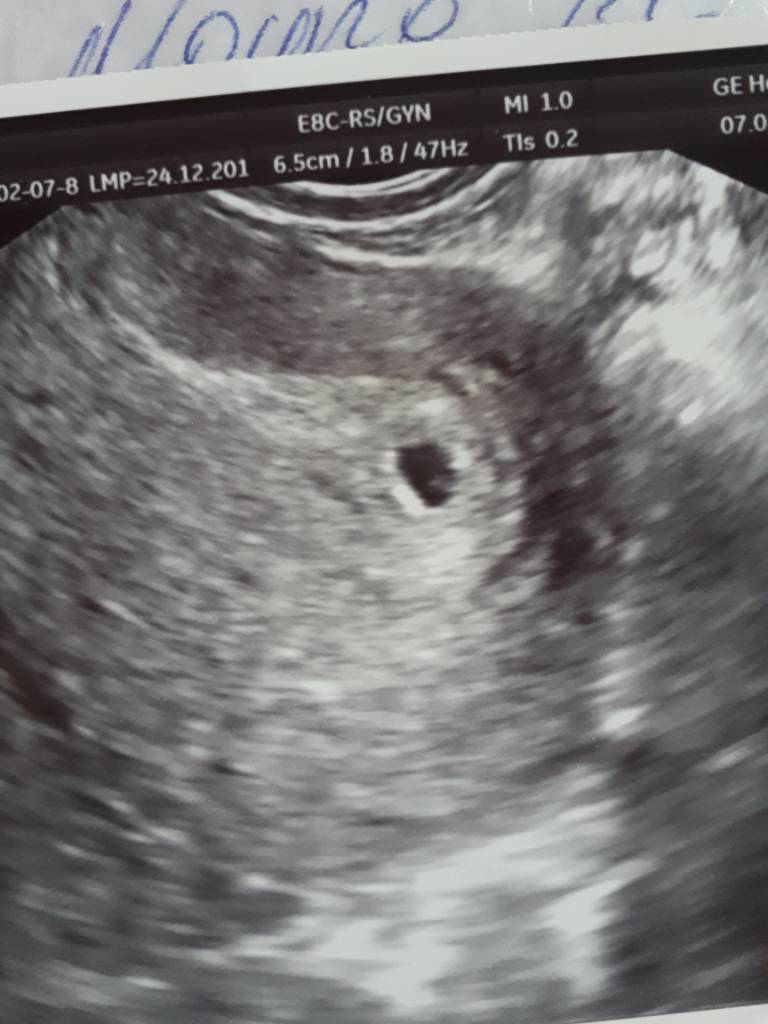

6tc na usg nie widać pęcherzyka

Nie wygląda to jak pęcherzyk, nawet jeśli ciąża byłaby młodsza to coś byłoby lepiej widać, jak to mój lekarz określa, w bardzo wczesnej ciąży widać coś do wygląda jak pierścionek. U mnie w 6tc było już słychać serduszko. Zrobiłabym betę, może masz możliwość iść do innego lekarza? Może to kwestia jakości sprzętu?

Dzięki dziewczyny w poniedziałek juz ide do dobrego lekarza. Bardzo sie martwię czy wszytko jest dobrze. I czy maleństwo jednak jest i zdroqo rośnie. To usg co wysłałam bylo robione w 4-5 tyg ciąży

To moje 4+4